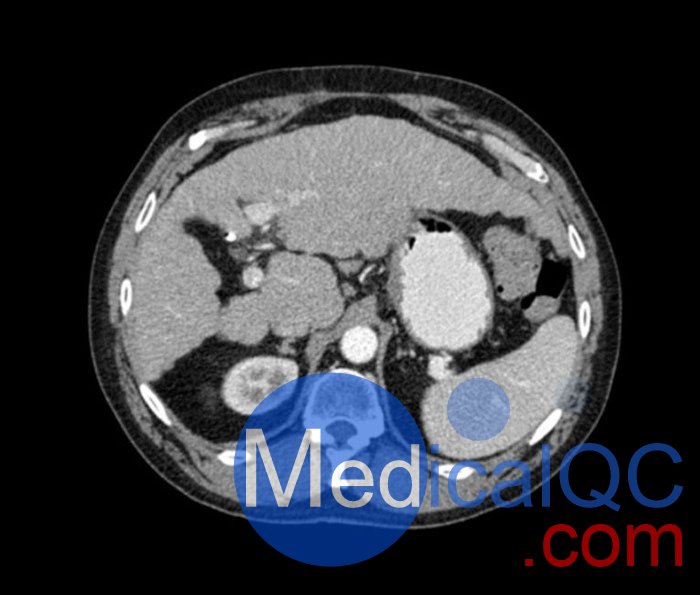

WEK53-04肝硬化腹部模體,WEK53-04門靜脈期腹部模體詳細(xì)介紹:

WEK53-04肝硬化腹部模體,WEK53-04腹部模體模擬了門靜脈期的造影劑增強(qiáng)腹部。它覆蓋了第十胸椎至第三腰椎。

WEK53-04肝硬化腹部模體,WEK53-04腹部模體代表膽囊切除術(shù)后的腹部,帶有小夾子。肝臟有肝硬化的典型體征,在第三腰椎水平植入下腔靜脈過濾器。兩個腎臟都有囊性病變,左側(cè)有一小塊腎結(jié)石。

該模型可用于 CT(包括 CBCT)以評估和優(yōu)化成像性能和后處理應(yīng)用,包括支持 AI 的應(yīng)用。它也適用于培訓(xùn)目的。

該模型提供了對軟組織和骨組織的詳細(xì)而逼真的模擬??障吨刑畛渲s-160HU的纖維素-聚合物復(fù)合材料。

WEK53-04肝硬化腹部模體,WEK53-04門靜脈期腹部模體診斷特征

真實(shí)模擬脈管系統(tǒng)、骨骼和軟組織,包括肝臟、胰腺、脾臟、腎上腺、腎臟、胃、小腸和結(jié)腸。

• 肝硬化

• 膽囊切除術(shù)

• 下腔靜脈濾器

• 腎囊腫

• 腎結(jié)石

• 淋巴結(jié)腫大

WEK53-04肝硬化腹部模體,WEK53-04門靜脈期腹部模體產(chǎn)品成像圖: